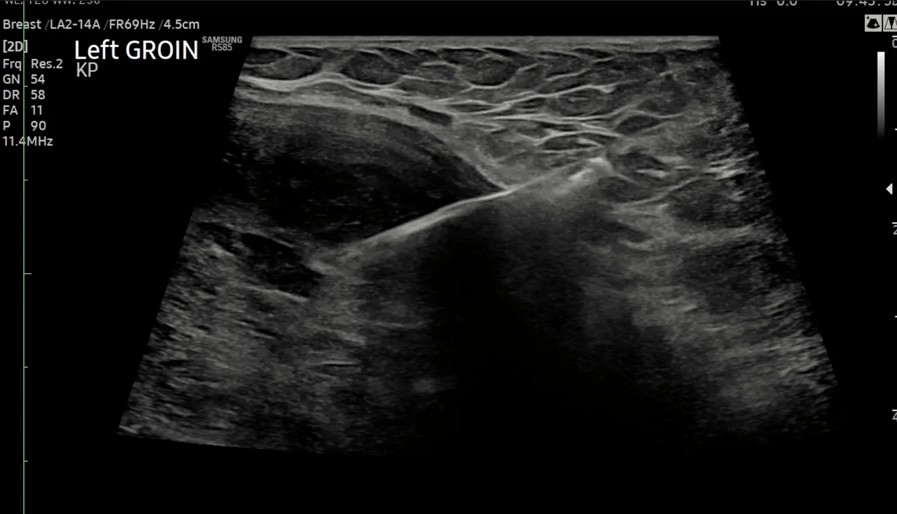

Fig.04. Ultrasound-guided core biopsy of the described left medial groin mass using B-mode extended field of view imaging.